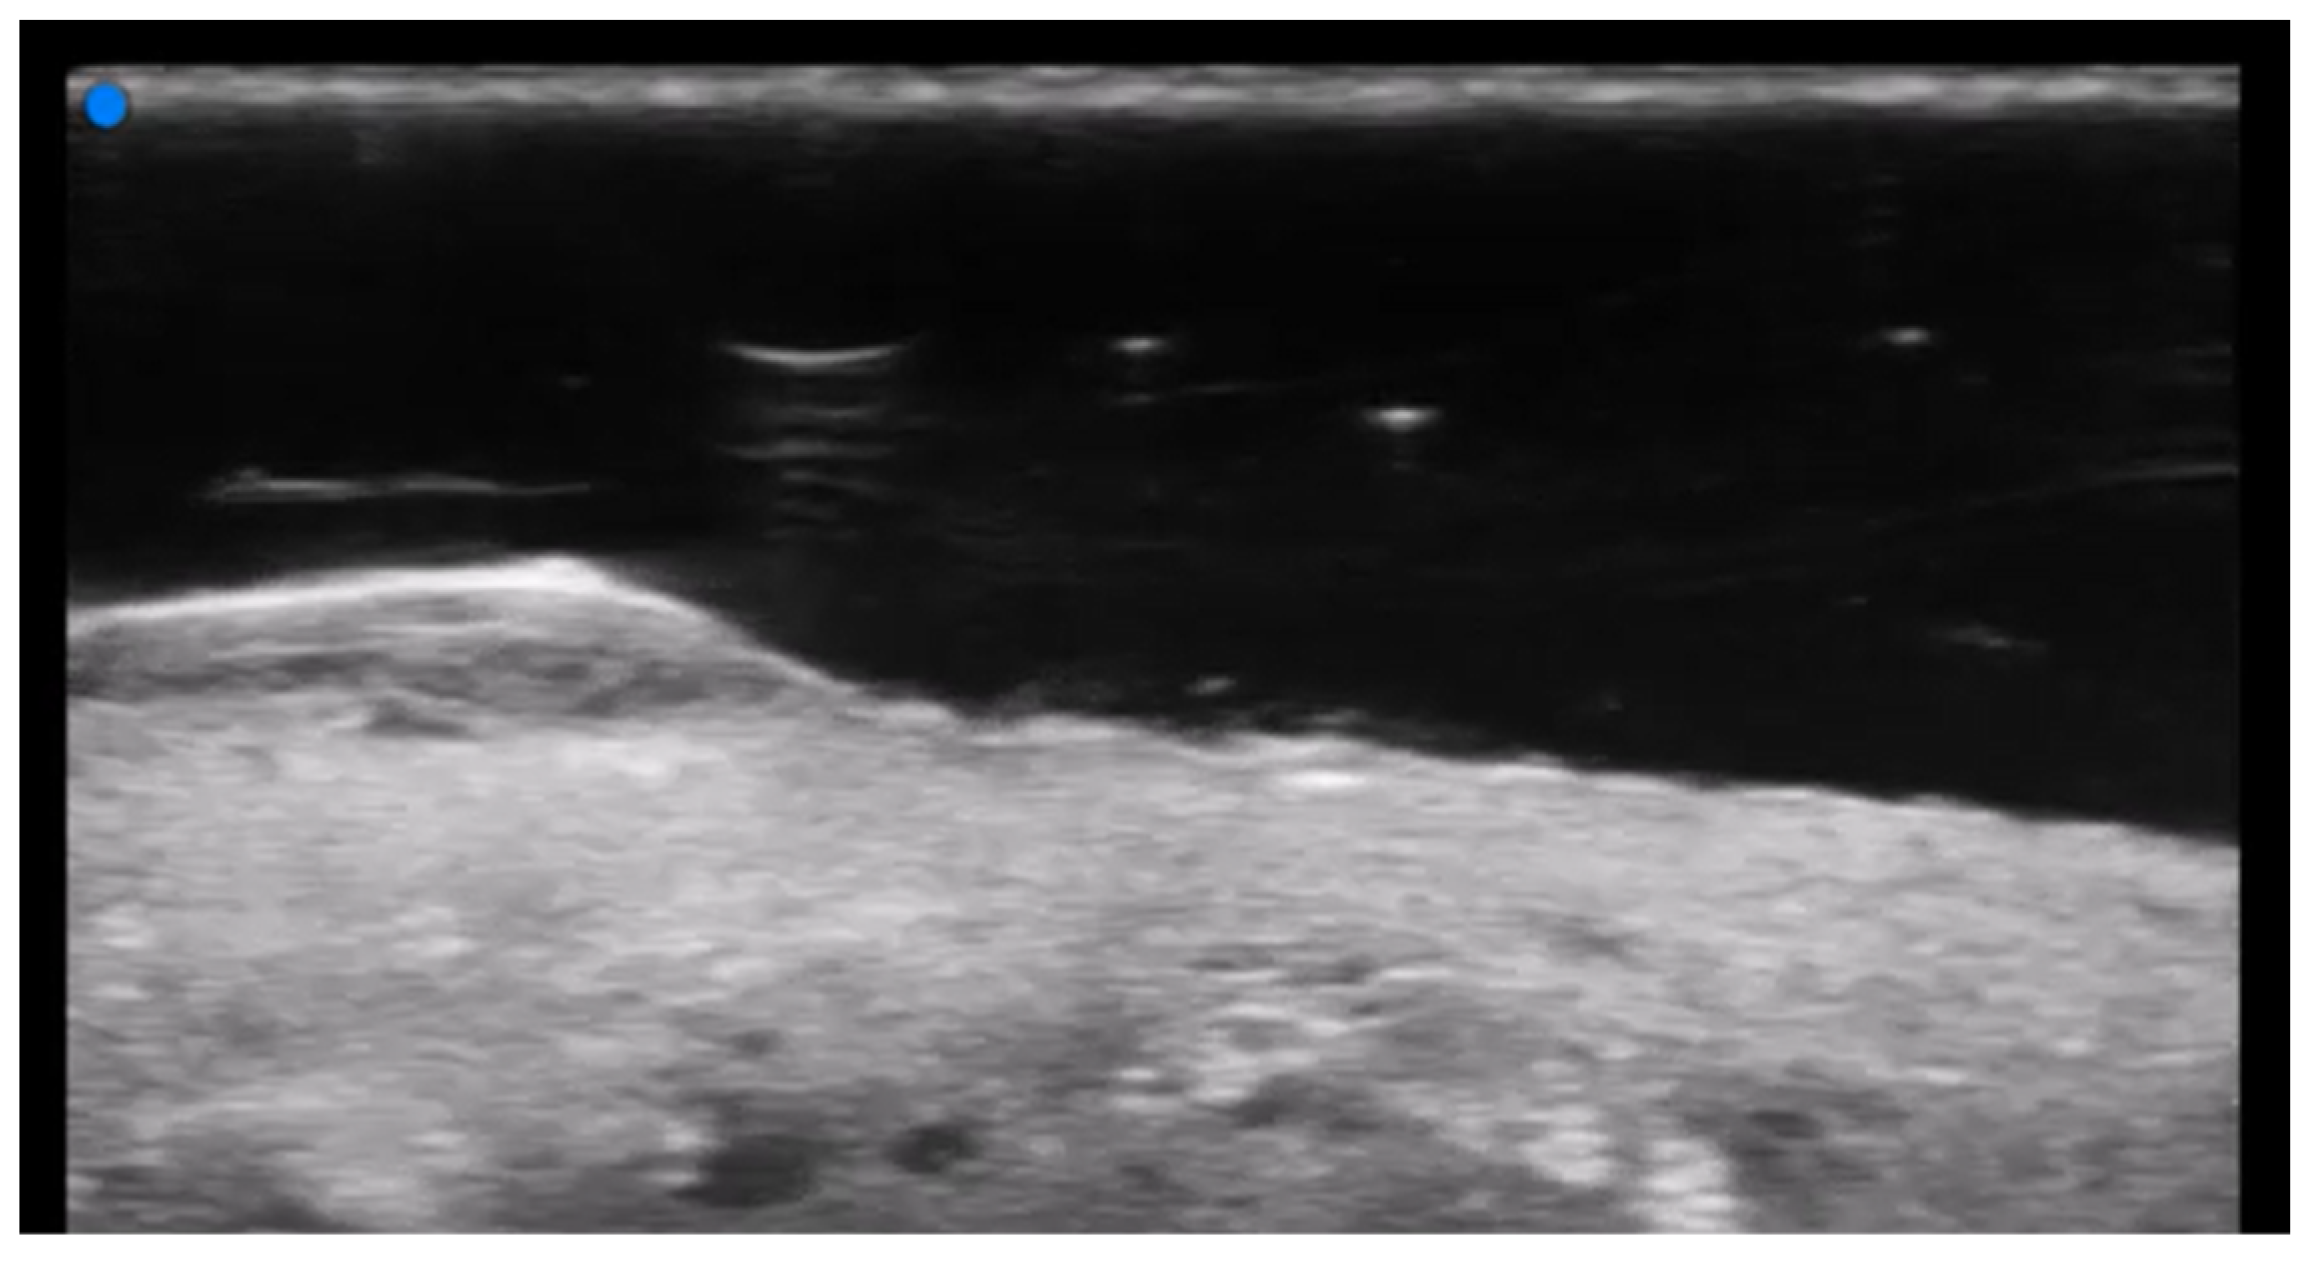

- Granieri, G.; Michelucci, A.; Manzo Margiotta, F.; Cei, B.; Vitali, S.; Romanelli, M.; Dini, V. The Role of Ultra-High-Frequency Ultrasound in Pyoderma Gangrenosum: New Insights in Pathophysiology and Diagnosis. Diagnostics 2023, 13, 2802. [Google Scholar] [CrossRef] [PubMed]